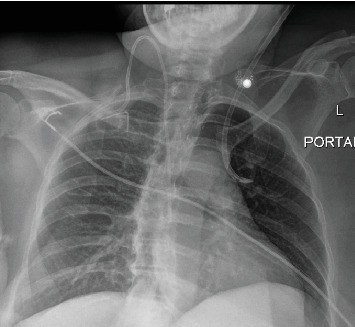

Background: Partial anomalous pulmonary venous connections are embryologic defects in which the normal connection between the pulmonary veins and left atrium is disrupted. These rare anomalies are often asymptomatic and identified incidentally. The most common variant is a connection between the left upper pulmonary veins and the left innominate vein. Although typically asymptomatic, these variants are important to be aware of, particularly when performing procedures involving the venous anatomy. Case Presentation: We present the case of a 52-year-old female with a previous history of colon cancer who underwent right hemicolectomy and presented to the hospital due to severe dehydration secondary to profuse nausea, vomiting, and diarrhea. She developed an acute kidney injury with electrolyte derangement and metabolic acidosis requiring initiation of hemodialysis. Due to her preexisting right internal jugular port access, the decision was made to proceed with left internal jugular dialysis catheter access. Central venous access was performed in standard fashion. There was venous-appearing blood return at the time of needle access and subsequent dilations. However, at the time of catheter advancement, there was noted return of bright red blood and resistance to advancement, concerning for possible arterial cannulation. Concerning arterial placement, an arterial blood gas (ABG) test and chest x-ray were performed; however, the transducer waveforms were not consistent with this. Computed tomography angiography obtained revealed left internal jugular venous access with catheter extension into an anomalous pulmonary vein within the left upper lobe. The patient was taken to the angiography suite and under fluoroscopy guidance had new left internal jugular catheter access with the catheter terminating successfully in the superior vena cava. She underwent successful dialysis and was subsequently discharged on postprocedure Day 8. Conclusions: Central line placement is a commonly performed procedure in hospitals. There are steps that have been developed to limit complications for this procedure, including ultrasound guidance, visualization of venous blood, and confirmatory imaging prior to use. This is a case in which arterial-appearing blood, paO2, and chest x-ray were concerning for incorrect placement, but additional imaging revealed accurate access with anomalous anatomy. Overall, the case of central line placement in anomalous pulmonary venous connections is rare but needs consideration when the clinical scenario is appropriate.